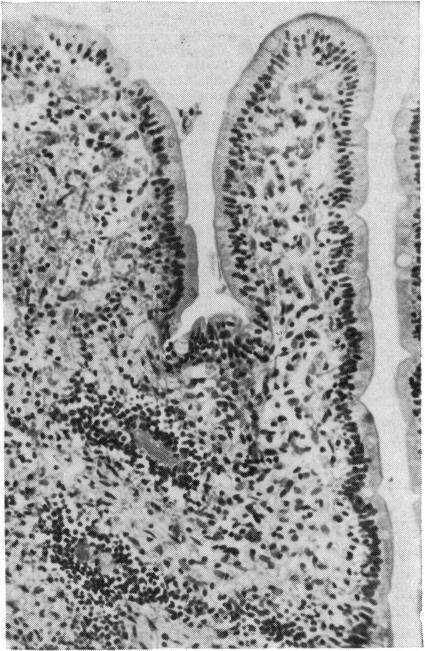

Two cases of Whipple's disease are reported in which a parallel course is confirmed between the clinical and ultrastructural findings. This is not so with light microscopy since it takes much longer for these findings to return to normal. In case 1, the presence of bacilli circulating freely in the sinusoid of a lymph node is described. Case 2 demonstrates the existence of special granulomata formed by atypical macrophage histiocytes which appear in coagulative necrosis together with a closely adherent crown of lymphocytes. Furthermore, these histiocytes have moved towards the deepest part of the lamina propria, and have become dissociated from the muscularis mucosae causing a diverticulosis of the small intestine.

报告了两例惠普尔病,其临床和超微结构检查结果呈现平行关系。而光学显微镜检查则不然,因为这些结果恢复正常所需时间长得多。病例1描述了杆菌在淋巴结窦中自由循环的情况。病例2显示了由非典型巨噬细胞组织细胞形成的特殊肉芽肿的存在,这些细胞与紧密附着的淋巴细胞冠一起出现在凝固性坏死中。此外,这些组织细胞已向固有层最深部移动,并与黏膜肌层分离,导致小肠憩室形成。